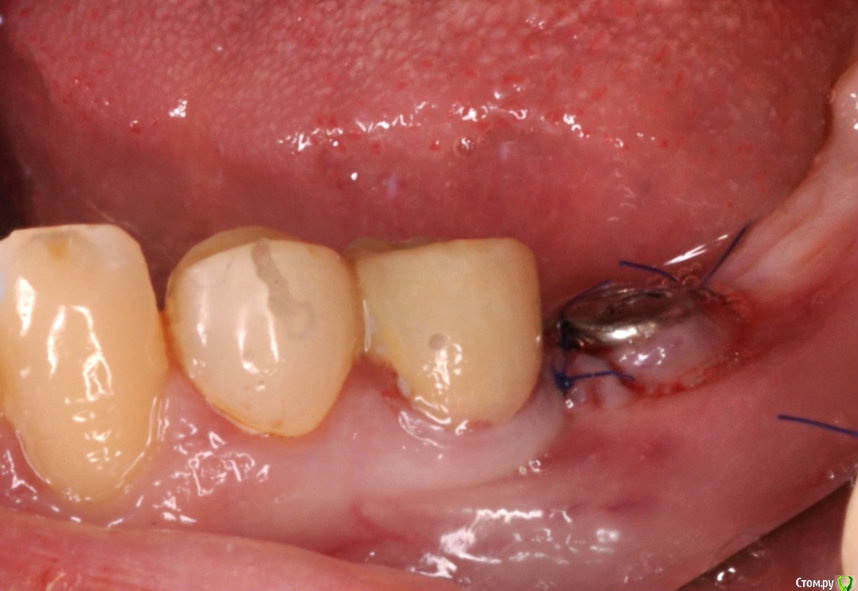

Neilrus Опубликовано 28 марта, 2017 Поделиться Опубликовано 28 марта, 2017 (изменено) Здравствуйте, коллеги. Есть пациентка, 45 лет, принимает постоянно раз в две-три недели метотриксат путем инъекции по 2,5мл по причине ревматойдного артирта.установил ей одномоментно имплантат в позицию 11 зуба с небольшой пластикой вестибулярно. торк отличный, по прошествии 3 мес через день после очередного укола метотриксата вспыл маленький свищ с белесоватым отделяемым, открыл, проверил усилие выдержал 35Нсм, установил временную коронку с подворачиваним лоскута. Все стабильно 3 недели и вот вчера очередной укол и появляется свищ уже большего размера. Возможно это от данного препарата? есть у кого-нибудь опыт с такими пациентами? ПОчитал инструкцию и обомлел (особенно про часть где совмещение с НПВС может привести к летальному исходу), ее доктор финский считает что такое возможно, но отменить или заменить его возможности нет.Она живет в финляндии раз в месяц только приезжает, рентгена нет, общаемся по вайберу, фото пока только такое, приедет ко мне 5 апреля. Изменено 28 марта, 2017 пользователем Neilrus Ссылка на комментарий

Neilrus Опубликовано 28 марта, 2017 Автор Поделиться Опубликовано 28 марта, 2017 времянка на временном титано-пластм аббатменте, не фигня какая-нибудь Ссылка на комментарий

kriokov Опубликовано 1 апреля, 2017 Поделиться Опубликовано 1 апреля, 2017 Ревматоидный и метатрексат.(тоже просил помощи у коллег) Болт в обл 36, суперлайн. фото с коронкой полгода назад ортопед сделалМне кажется свищи, это имплантат коронально "голый ", и слизистая тонкая, хотя всегда возможны другие факторы. 1 Ссылка на комментарий